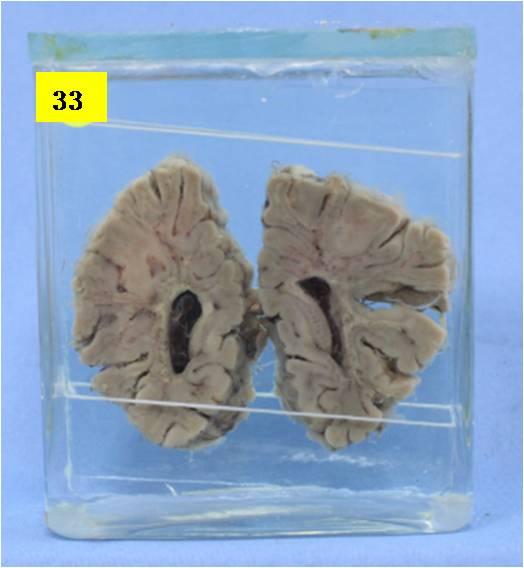

神经疾病-60-33. 先天性白质发育不良

大脑经基底节冠切,胼胝体下见侧脑室扩大,双侧侧脑室积血,其上方额叶部分脑回白质发育不良、纤细,其相应灰质菲薄